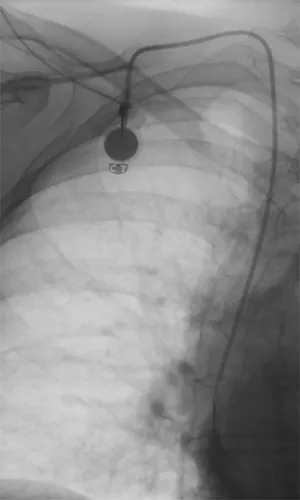

Portsystem rechts pektoral mit Spitze vor dem rechten Vorhof

Ein Portsystem ist ein kleines, implantierbares Gerät, das unter die Haut – pektoral oder im Oberarm – eingesetzt wird. Es besteht aus einer Kammer (Port) und einem dünnen Schlauch (Katheter), der in eine große Vene führt. Portsysteme ermöglichen den sicheren und einfachen Zugang zum venösen System, besonders bei langfristigen Therapien wie Chemotherapie oder regelmäßigen Infusionen.

Implantation Bei der Implantation wird das Portsystem unter sterilen Bedingungen ambulant oder stationär eingesetzt. Nach örtlicher Betäubung wird der Katheter in eine große Vene eingeführt, und die Kammer wird unter die Haut gesetzt. Das System wird sorgfältig fixiert und die Wunde verschlossen. Danach kann der Port für die Therapie genutzt werden, ohne dass jedes Mal eine neue Venenpunktion erfolgen muss.